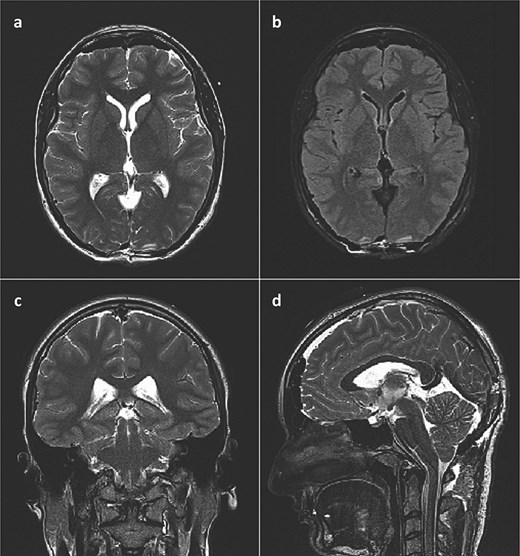

This finding was in concordance with a brain magnetic resonance imaging (MRI) done the previous day in another hospital which described hemosiderin deposits within the dorsal part of the cyst, with complete interruption of the cerebrospinal fluid (CSF) communication at the level of mesencephalic aqueduct, and a 4 mm long cerebral tonsil protrusion (Fig. 2).

Brain MRI scan. (a) T2 weighted image, axial slice, pineal cyst occupying posterior part of the third ventricle with hemosiderin deposits in the posterior part of the cyst; (b) FLAIR image, axial slice, showing different contents inside the cyst when compared to CSF; (c) T2 weighted image, coronal slice, pineal cyst inside the lower part of the third ventricle, beneath internal cerebral veins; (d) T2 weighted image (SPACE), sagittal slice, showing pineal cyst in front of a rather large vein of Galeni, and compressing the cranial part of the cerebral aqueduct.